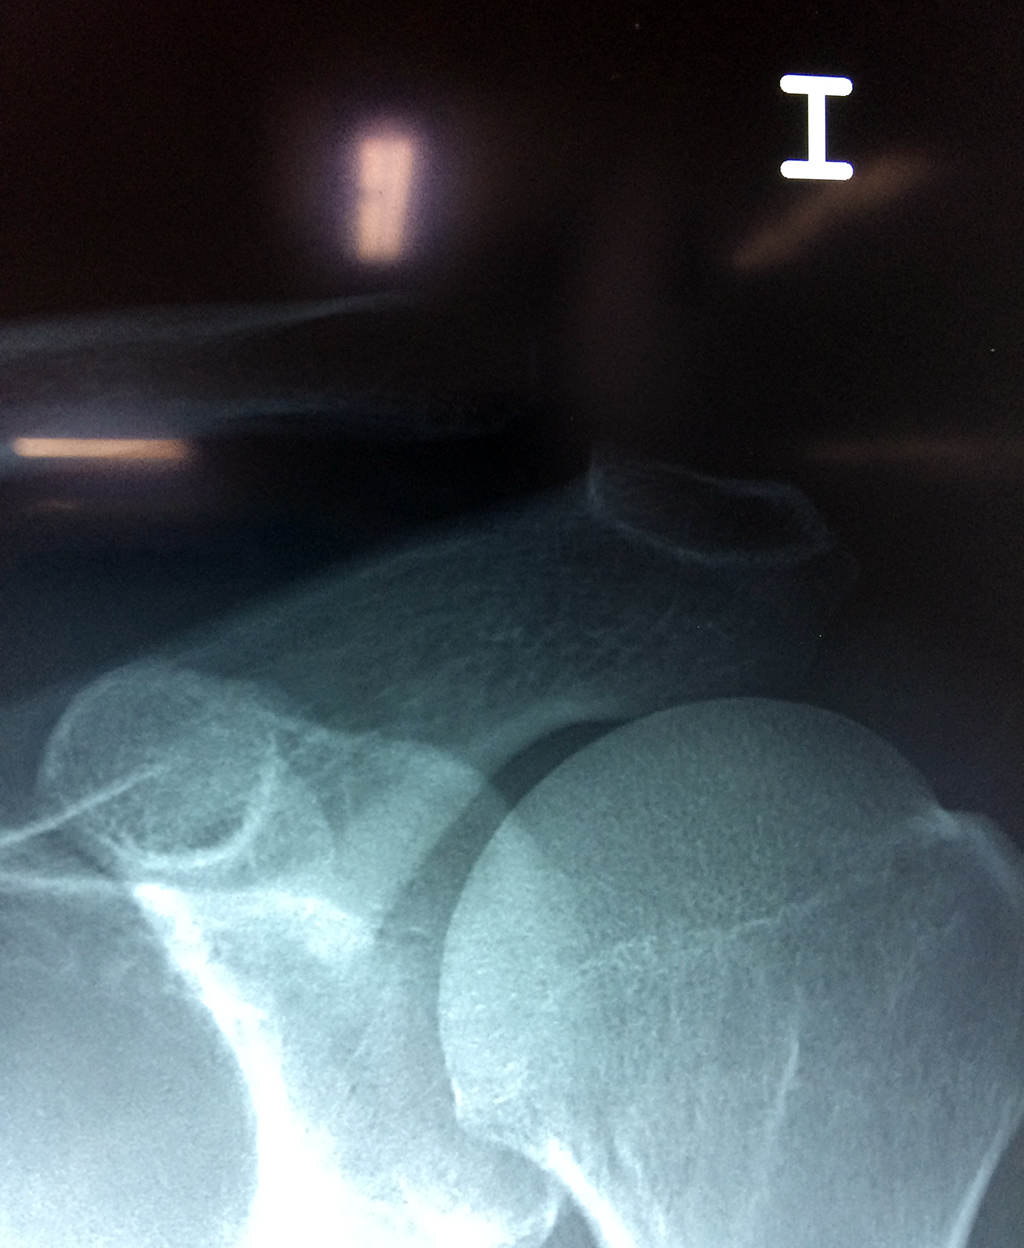

Cirugias en El Salvador - Clavícula